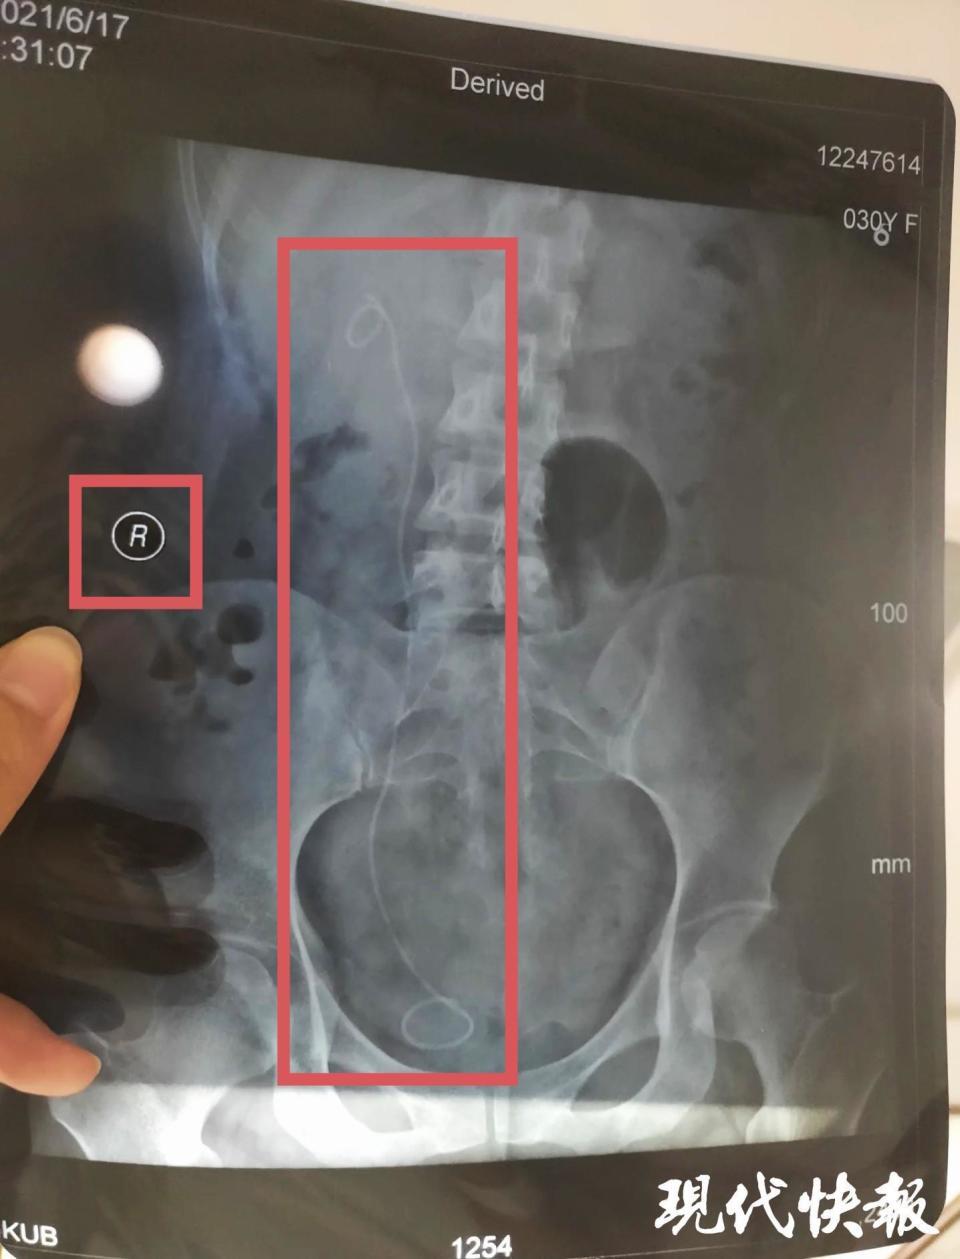

盐城市民朱女士因左侧输尿管狭窄伴左肾积水,前往复旦大学附属华山医院诊治,办好一系列手续后,2021 年 4 月 19 日住院,4 月 21 日签订手术知情同意书。手术知情同意书显示,拟对左侧输尿管镜检备扩张 / 内切开。直到出院一个多月后复查时,她才意外发现,手术期间,医生竟然 " 把左右给搞错了 ",在右侧输尿管无异常的情况下,医生在右侧输尿管内安装了支架管。

最终,这起医疗事故经上海市静安区卫生健康委员会移交上海市医学会组织鉴定,认定朱女士遭遇构成四级医疗事故,医方承担完全责任。当初,参与这起手术的医生共三人,包括主刀医生姜某某、一助胡某以及二助邹某某。令朱女士没想到的是,2022 年 7 月,上海市静安区卫生健康委员会对这起医疗事故中一助胡某作出 " 警告 " 的行政处罚。理由是作为这起医疗事故的责任医师,胡某违反了卫生行政规章制度或者技术操作规范,造成严重后果。